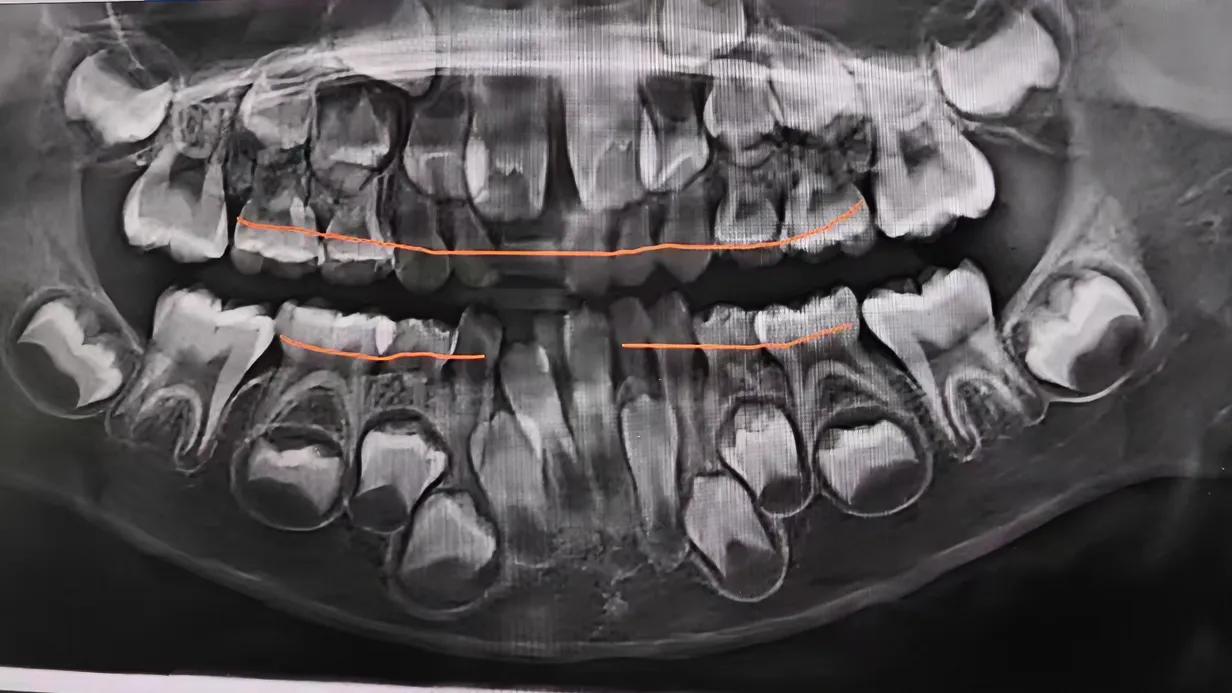

小孩子治牙这么贵的呀!

上次看到一篇贴子,给小孩花三万到五万矫正牙齿都舍不得的家庭,大有人在,而且占绝大多数。几千条的评论各个ip都有,真感觉不出来中国中产和小康占了多大比例。

今天去孩子学校,跟家长聊天才知道,在牙上花个大几千的都算少的。什么根管治疗、牙齿矫正各种烧钱啊。这才二年级啊!

没记得小时候有这么多问题吧!还是那时候对口腔保护、认知不够?怎么现在孩子都是一口烂牙呢?

有人说是食物太过丰富,点心、饼干、饮料搞的。也有人说跟肾气有关!更多人说的是刷牙不到位。